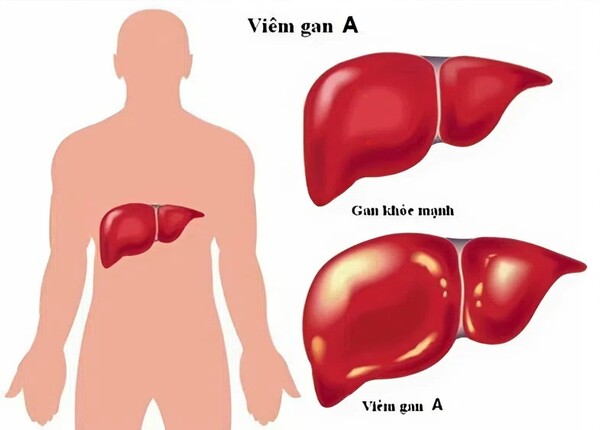

Bệnh viêm gan: Nguyên nhân và những lầm tưởng dễ mắc phải

Viêm gan là tình trạng viêm và tổn thương tế bào gan, làm suy giảm các chức năng quan trọng của gan như chuyển hóa, thải độc, dự trữ năng lượng và điều hòa hoạt động sinh lý toàn cơ thể. bệnh viêm gan có thể do nhiều nguyên nhân gây ra, bao gồm: nhiễm ...